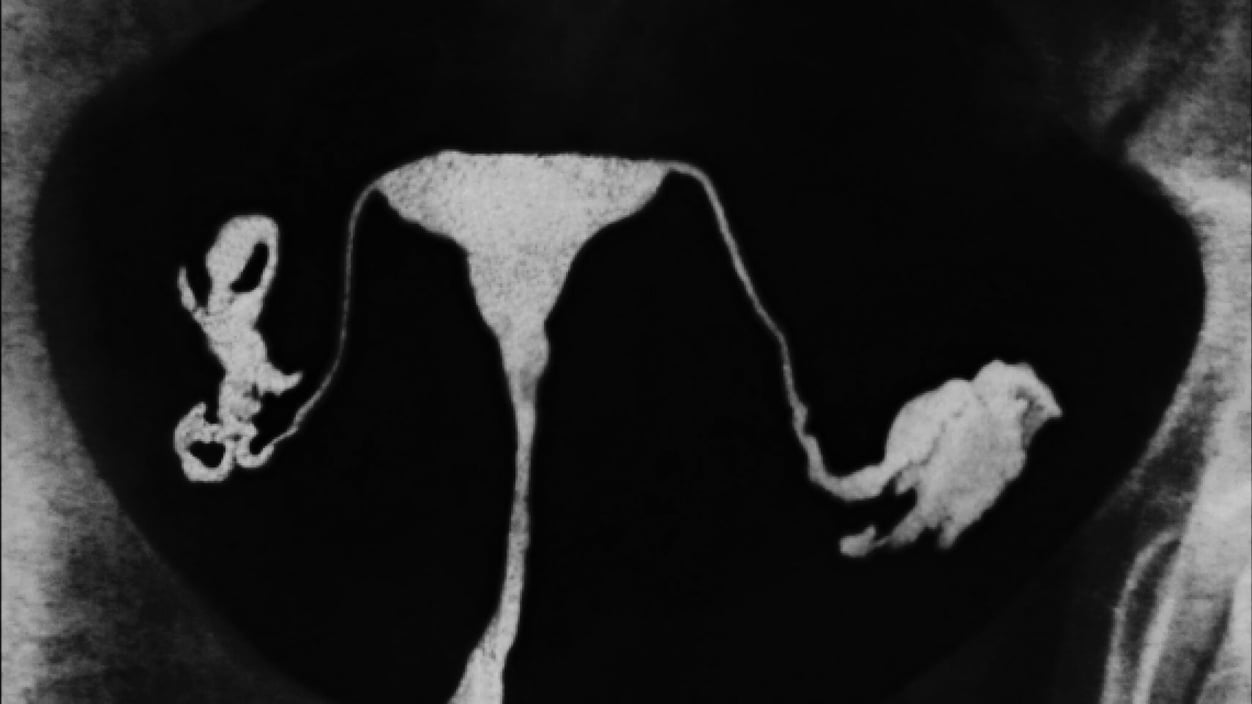

Despite the name, most ovarian cancers actually start in the fallopian tubes — those widening flumes with tentacle-like fringes at the end, as STAT's Eric Boodman describes them, which connect someone's ovaries to their uterus. The reasons for this aren't entirely clear. One hypothesis says that, in order to burst out of an ovary in the first place, the egg may be equipped with some sort of tissue-eroding chemical. Which means that over the course of ovulation, fallopian tubes get a repeated dose of whatever that cocktail may be.

With possibilities like these in mind, the removal of fallopian tubes — rather than simply tying them — has emerged as a promising, effective, preventative procedure. But there are a few problems. There haven't historically been distinct diagnostic codes for these procedures. And while some patients have found ways to utilize that opacity to get around insurance denials, other patients may not know which procedure they've gotten until long after the fact.